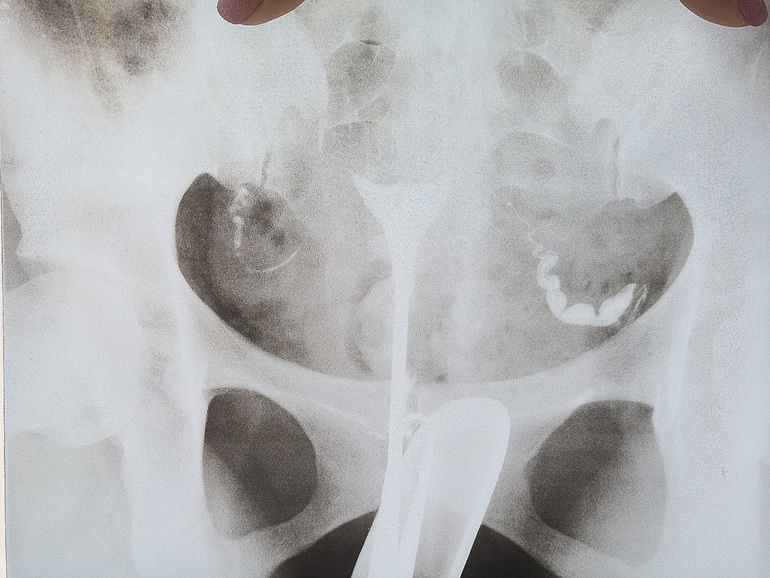

Проходимость труб. Нужно мнение.